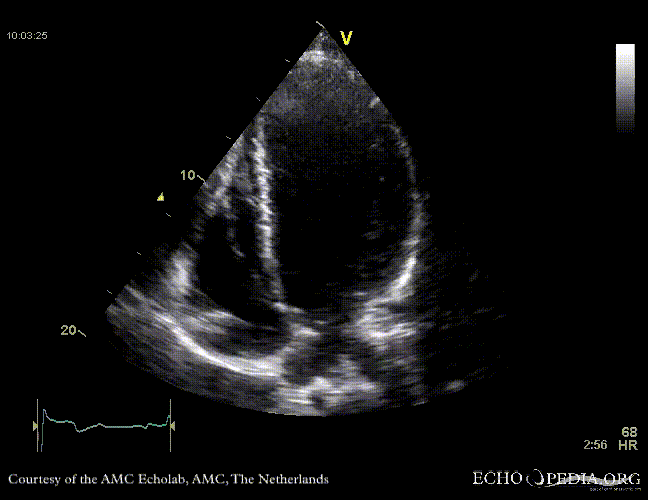

Case 10